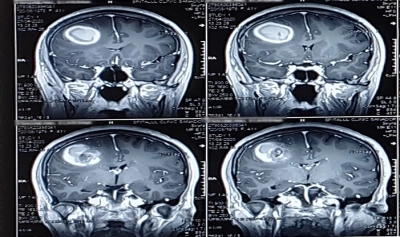

Consultațiile și investigațiile au mers ritmic. La Sanador se face medicină în echipă, în amănunt, eliminând orice intruziune. Tomografia a arătat o formațiune frontală dreapta, un cavernom format de un ghem vascular apărut insidios, devenit hemoragic. Nu trebuie să fii specialist pentru a realiza gravitatea situației. Dar trebuie să fii un profesionist redutabil pentru a rezolva calm și sigur un asemenea caz.